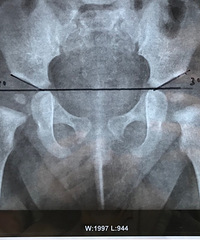

宝宝髋关节发育不良?说说我这一周的心痛经历 ,汲取我的教训

1个月前 收录

[[2020-03-08-09-59]][二级楼[2020-03-08-12-00]]

查看详情>>

阅读:4.3万回复:124